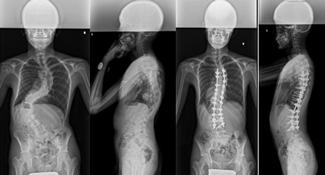

後方矯正固定術

せなかを切開してチタンなどで作られた椎弓根スクリューをせぼねに挿入して、ロッドと呼ばれる金属のバーで固定して、せぼねの矯正と固定を行います。術後に手術部の安静を保つために装具を3-6ヶ月程度着用します。

せなかを切開する場合が多いですが、状態によっては側方経路腰椎椎体間固定術(Lateral Lumbar Interbody Fusion: LIF)や、経皮的椎弓根スクリュー(Percutaneous Pedicle Screw: PPS)をはじめとした体への負担を軽減する手法も取り入れられています。

手術時間は4時間程度で、入院期間はこどもの患者様で2週間程度、大人の患者様では2週間程度で場合によってはリハビリテーション病院へ転院をして頂き、さらにリハビリテーションを行います。

-

こどもの特発性側弯症に対する後方矯正固定術 -

大人の側弯症に対する後方矯正固定術